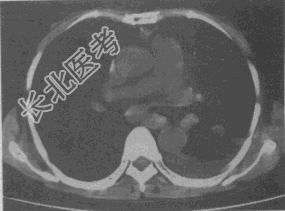

- 单项选择题女,55岁, 胸痛伴咯血丝痰1周,胸部CT如图, 最可能的诊断为

A、转移性肺癌

B、左侧周围型肺癌并肺内转移

C、左侧中央型肺癌并肺内转移

D、多发性肺脓肿

E、结节病